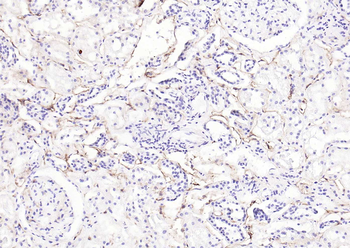

IHC staining of FFPE human prostate carcinoma with CD73 antibody (clone NT5E/2545). HIER: boil tissue sections in pH9 10mM Tris with 1mM EDTA for 10-20 min and allow to cool before testing.